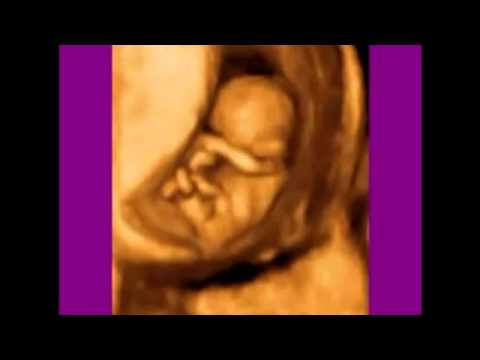

Ecografía 4D (9 semanas)